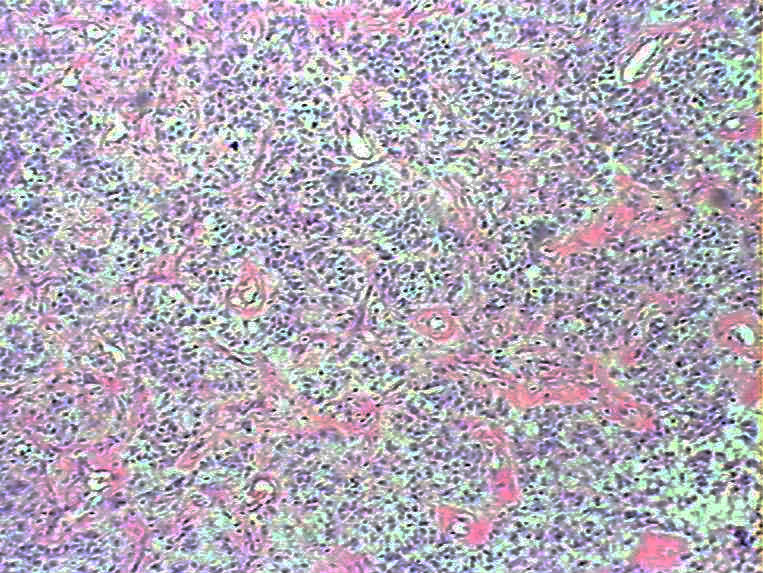

腹部肿物会诊血管球瘤

女45发现下腹部皮下肿物4个月

灰白色肿物一枚,9*8*5cm,切面实性、质韧,似有包膜

• 腹部肿物会诊血管球瘤图1

图1

血管球瘤